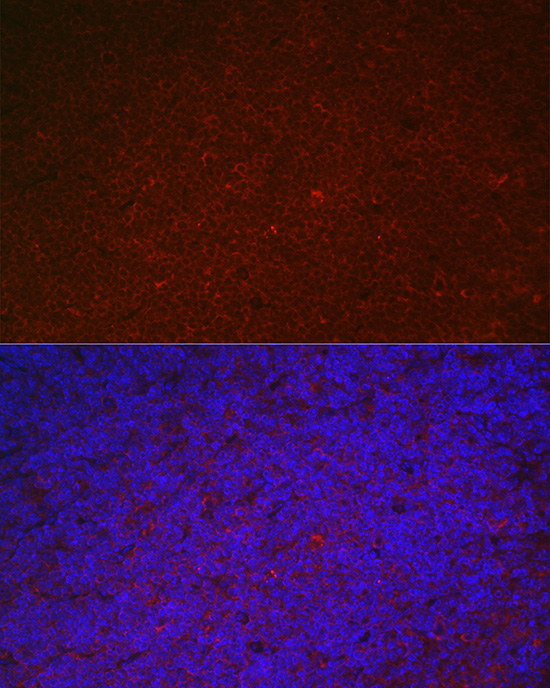

Immunofluorescence analysis of mouse spleen using LILRB4 Rabbit pAb.